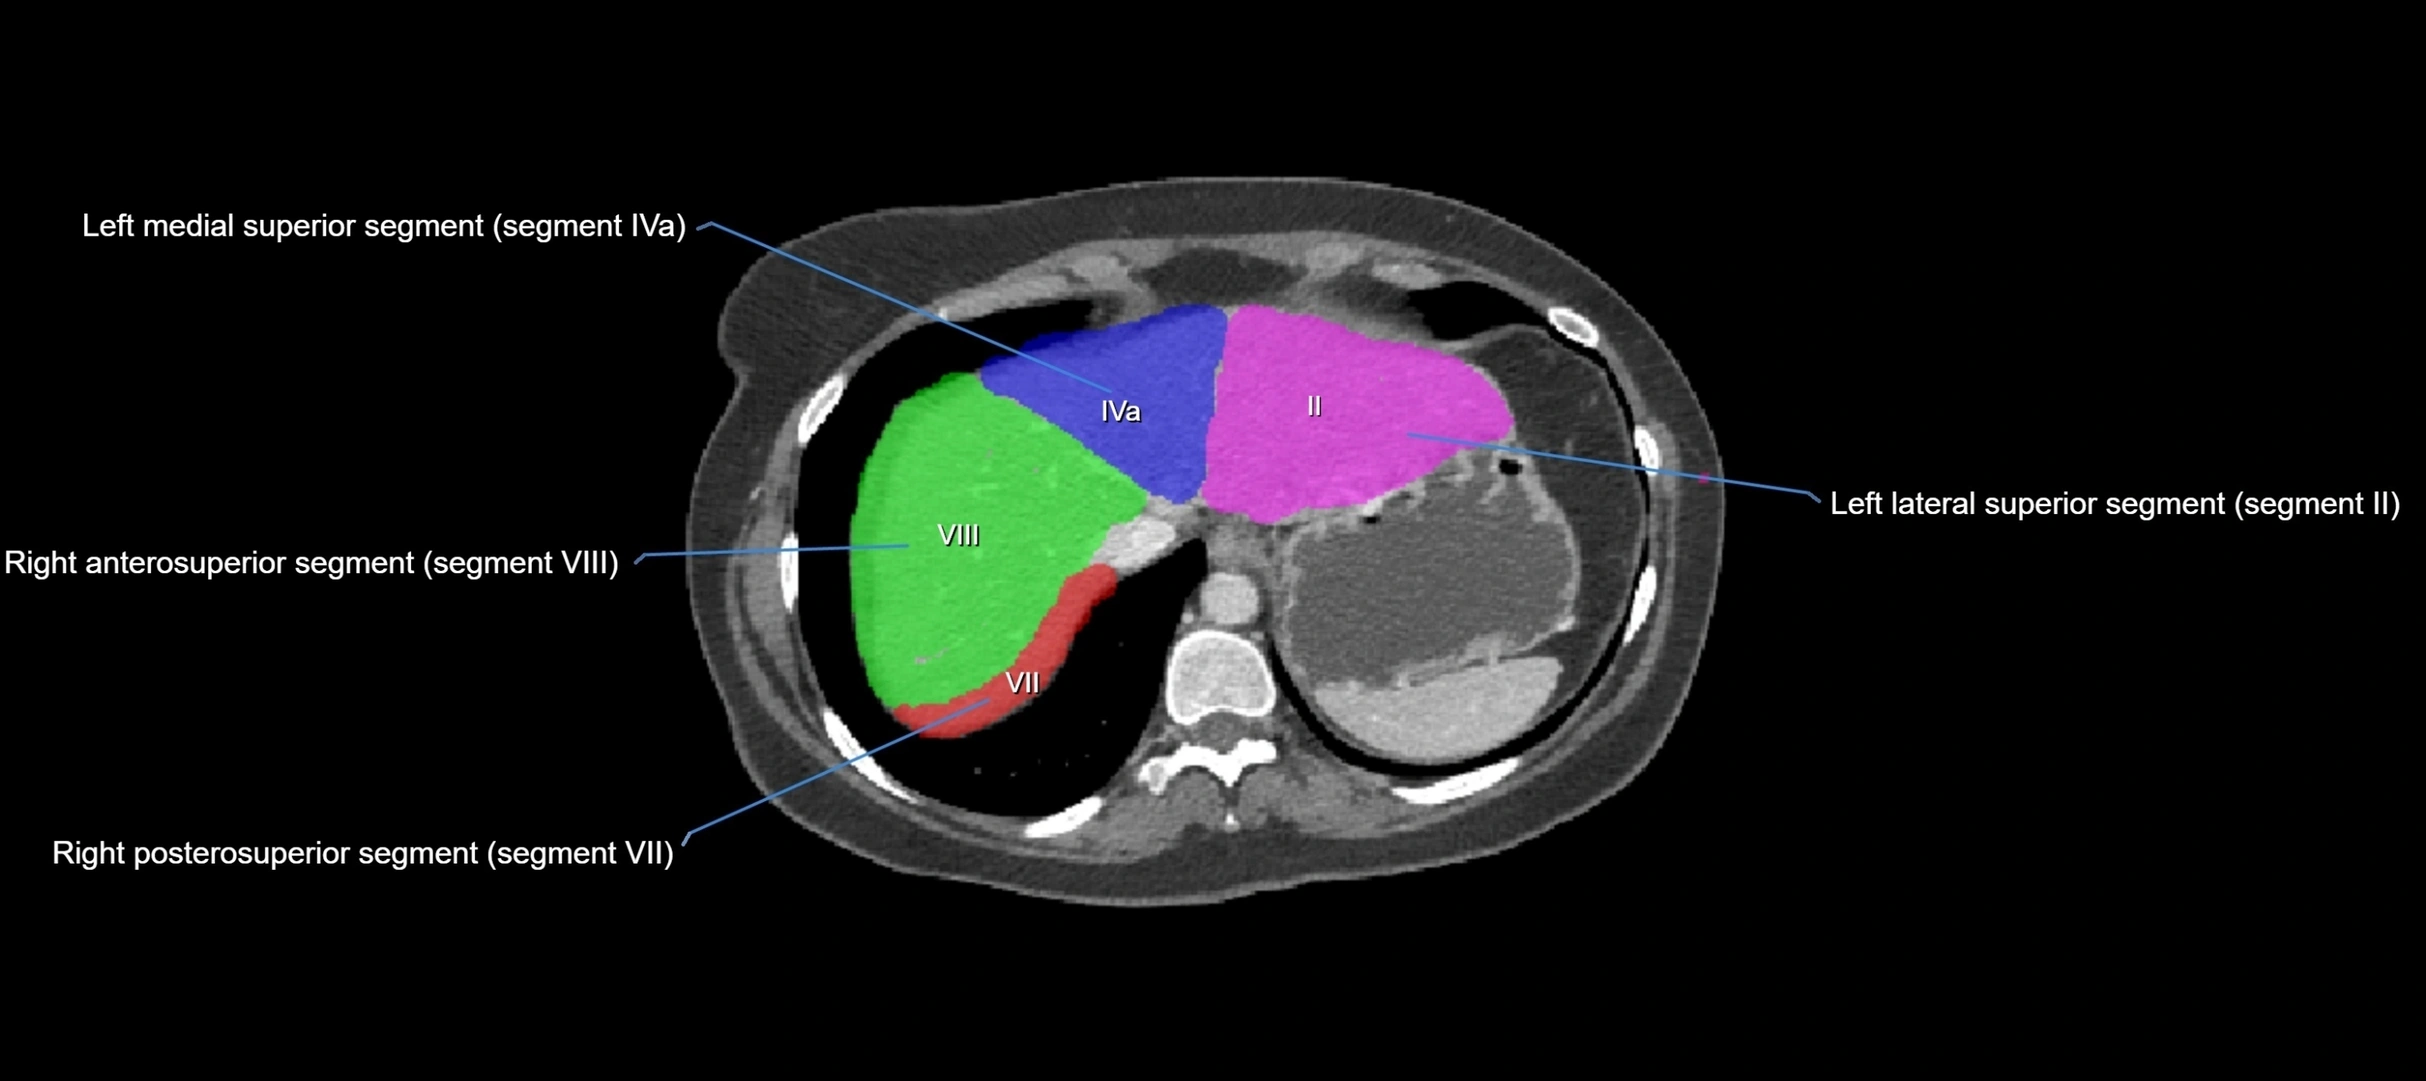

CT Appearance

CT Pre-Contrast:

• Caudate lobe appears as a soft-tissue density, isodense to the rest of the liver

• Enlargement may be appreciated in cirrhosis or Budd–Chiari syndrome

CT Post-Contrast:

• Homogeneous enhancement in the portal venous phase, similar to rest of liver

• Independent venous drainage into the IVC may be visualized

• Lesions follow characteristic CT enhancement patterns (HCC: arterial hyperenhancement with washout; hemangiomas: peripheral nodular enhancement with centripetal fill-in)

CT Image

image